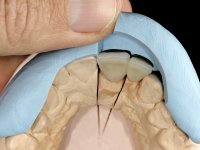

Fifty year old male patient, non-smoker. Carries a Maryland Bridge replacing tooth 2.2. "Maryland wings" are metallic and the dental surfaces in contact with them are infiltrated. Tooth 2.1 had a feldspathic ceramic veneer covering the vestibular surface. Tooth 1.2 presented a feldspathic ceramic veneer with exposed cervical margin. The edentulous space corresponding to tooth 2.2 is narrow and tall. Patient presents an open anterior bite, good oral hygiene and reasonable periodontal health.

Arcade prints were made with irreversible hydrocolloid, for the lab to prepare an acrylic provisional bridge, with tooth 2.1 as abutment and tooth 2.2 as cantilever pontic. A palatal support was made to be bonded with the palatal surface of tooth 2.3. After removal of the Maryland bridge and the vestibular veneer from tooth 2.1, the dental abutment was re-prepared by making the cervical finish line intrasulcular. The provisional bridge made in the lab was relined on the mouth with self-curing acrylic and composite resin. During 6 weeks the soft tissues were worked and stabilized, preparing the consultation for impression. In this session, gingival separation was performed with kaolin paste, using the provisional bridge to compress the material into the gingival sulcus. Impression was performed using wash technique, and the provisional bridge was placed. At the end of the consultation, an impression was made from the provisional bridge placed in the mouth, using irreversible hydrocolloid. The patient had approved the aesthetics of the provisional. This information was passed on to the lab, where the work followed a silicone index, based on the shape and arrangement of the provisional bridge, approved by the patient. The cantilever bridge was built with a Zr infrastructure, with particular care in designing the connector. After being tried and approved by the patient, the prosthetic was cemented in the mouth with resin modified glass ionomer.